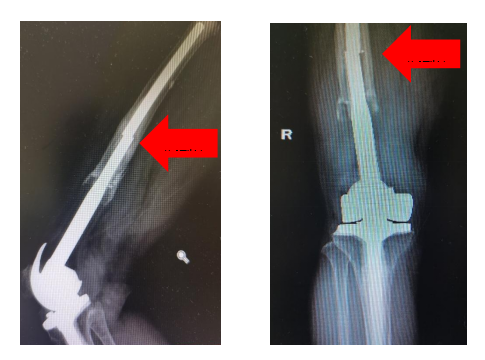

7月初,患者再次出现右大腿远端的疼痛,不敢活动,不能站立,右下肢活动时可听到异响,患者再次来到济宁市第一人民医院就诊,行X线检查显示为肿瘤假体股骨侧发生了断裂。

手术中,聂志奎主任团队通过在股骨远端2cm×1cm大小的开窗,巧妙的将断裂的股骨假体取出,并更换了新的肿瘤假体,避免纵劈股骨造成的手术创伤及经济负担,术中无任何血管神经损伤,手术取得圆满成功。术后3天,患者已经能在助行器的帮助下下地行走。